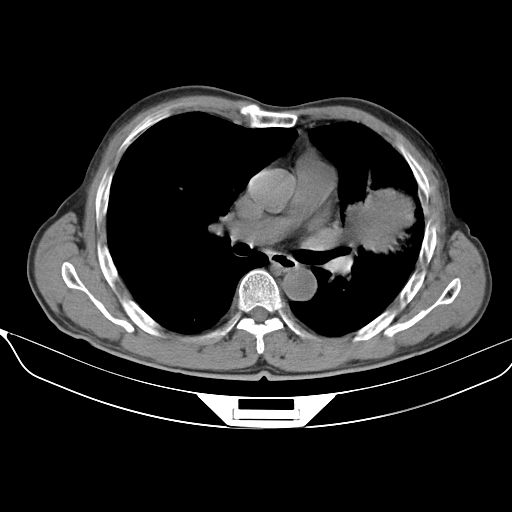

以下是引用心路寻觅在2010-3-1 10:23:00的发言:[br]1、考虑左肺上叶周围型肺癌[br]2、右上肺陈旧性病灶。[br][br][本贴已被 心路寻觅 于 2010-3-1 10:40:18 修改过]

以下是引用shuiyuan在2010-3-1 10:45:00的发言:[br]考虑左肺上叶中心型肺癌伴阻塞型炎症,邻近胸膜受侵。